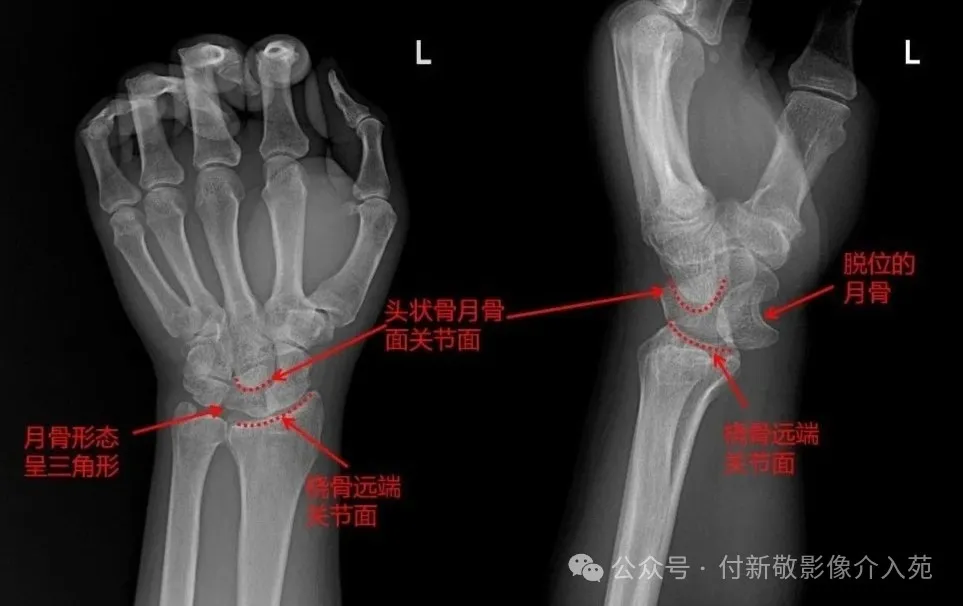

五、腕关节脱位

腕关节脱位:手腕在屈腕状态下遭受较大冲击力,如高处跌落、摔倒、车祸时等,使着力点集中于头月关节,致使头月骨周围的掌背侧韧带发生断裂,发生尺桡骨远端骨折和腕关节及腕骨脱位。

患侧腕部明显肿胀疼痛,手腕关节活动功能丧失,伤及神经时,可有神经分布区麻木感。

腕关节X线检查:首选检查,可明确诊断腕关节组成骨及诸腕骨是否存在脱位及骨折情况。